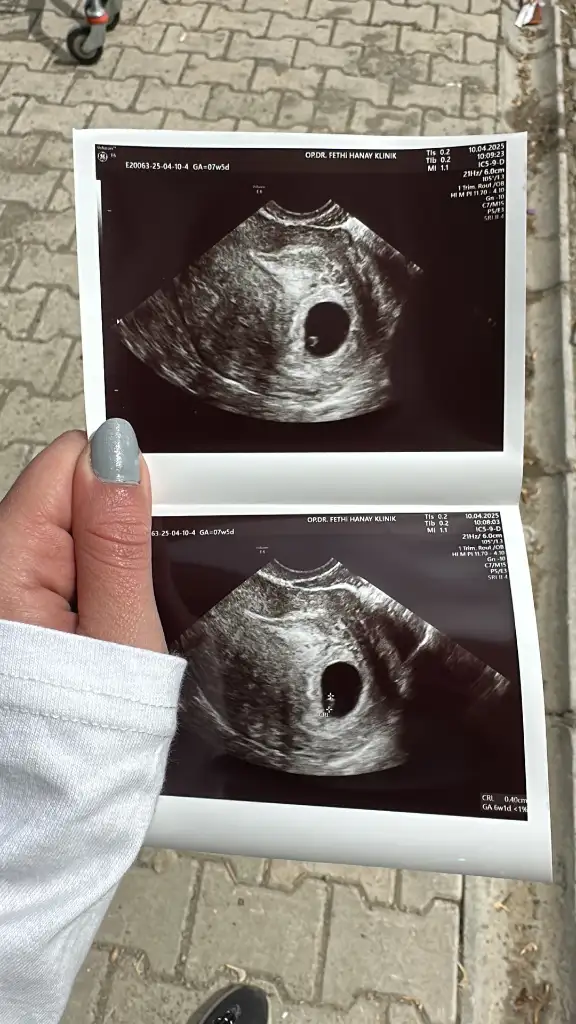

Herkese Merhaba son adet tarihim 22 şubat, 6 haftalık gebeyim bugün kontrole gittim kese 15 mm yolk kesesi de 5 mm , kese büyümem iyi dedi doktor ama bebeği göremedi geç döllenme olabilir haftaya tekrar gel dedi. Boş gebelik olabilir mi dedim olabilir dedi, önlem amaçlı progesteron hap be fitil verdi

kanamam hiç yok yine de kullan dedi. Böyle olup da ilerkş haftalarda bebeği gören var mı ? Biraz endişelendim ve üzüldüm , yardımcı olursanız sevinirim 🌼

Benim de normalde 7 haftalık hamile olmam gerekirken bebek 6 haftalıkmış, haftaya gel görmemiz gerekiyor dedi, yolk sacı göründü, kese gayet düzgün denildi ama bebek yoktu